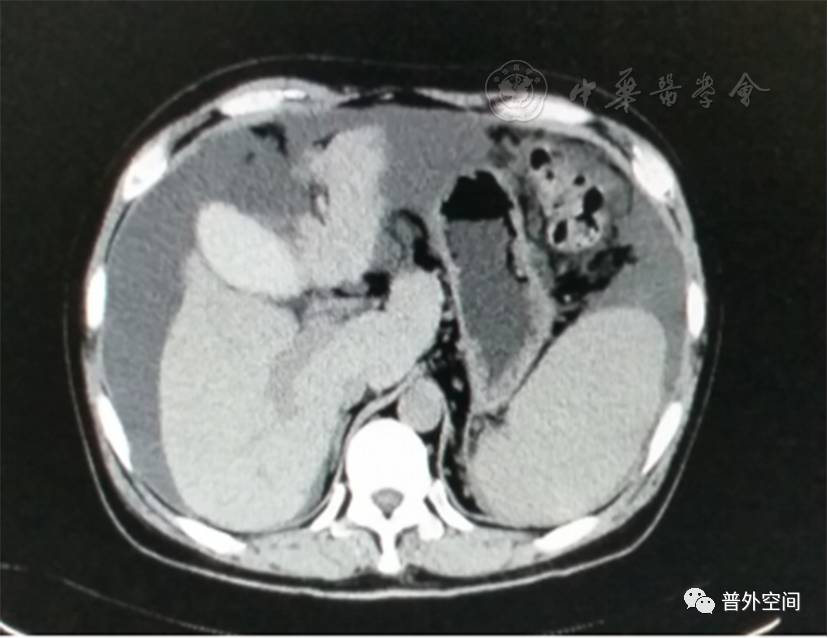

我们将这种方法应用到100多例没有艾滋病病毒感染的一般肝硬化患者身上,结果收到更好的疗效。例如1例男性患者,56岁,失代偿期肝硬化大量腹水合并脐疝(见封四,图1)。CT检查提示肝脏明显萎缩,肝脏体积1 302 ml,大量腹水,脾脏肿大(见封四,图2)。在多家医院就诊后都认为需要做肝移植。我们对患者进行脾切除加脐疝修补,自体骨髓经门静脉输注治疗。手术后3个月,肝功能Child-Pugh分级从C级转成*级A**,手术后1年,肝功能正常,腹部伤口愈合良好(见封四,图3)。CT检查提示肝脏明显增大,体积1 796 ml,腹水基本消失(见封四,图4)。对于肝功能C级的患者手术风险比较高,围手术期输注白蛋白、凝血酶原复合物、纤维蛋白原,改善肝脏功能,手术中经胃网膜右静脉插管埋置骨髓输注装置,输注自体骨髓。随着自体骨髓干细胞在肝内发生复杂的变化,肝硬化组织中的胶原纤维被降解和吸收,肝脏组织的增生和体积增大,肝功能好转,门静脉压力会逐渐降低。但是在手术后1年内,仍然有可能随时发生上消化道出血,需要经胃镜检查,套扎食管黏膜下明显曲张的静脉血管。这样我们做脾脏切除解除脾功能亢进,不做贲门周围血管离断,减少了手术损伤。食管黏膜下静脉曲张用胃镜下套扎治疗。待肝硬化逐渐逆转,食管黏膜下静脉曲张程度将会逐渐减轻。

图2 手术前腹部CT断层照片